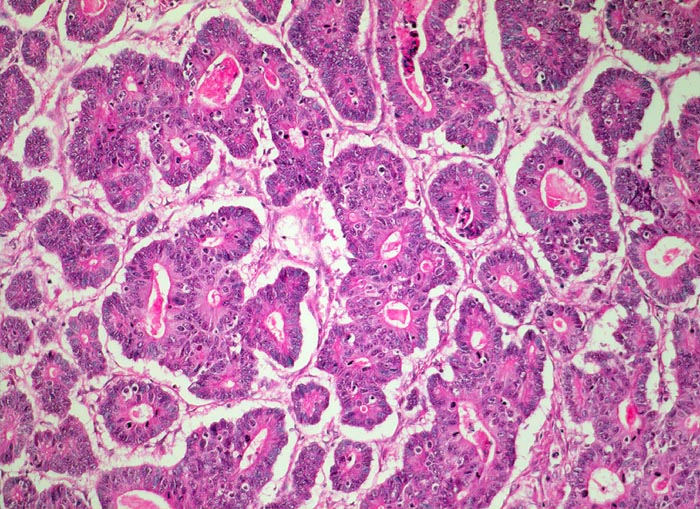

Adenokarzinom intestinaler Typ nach Lauren

Das Karzinom bildet dos à dos liegende tubuläre drüsige Strukturen ähnliche einem Kolonkarzinom.

Polypoider Tumor im Magenantrum.

Histologie

100